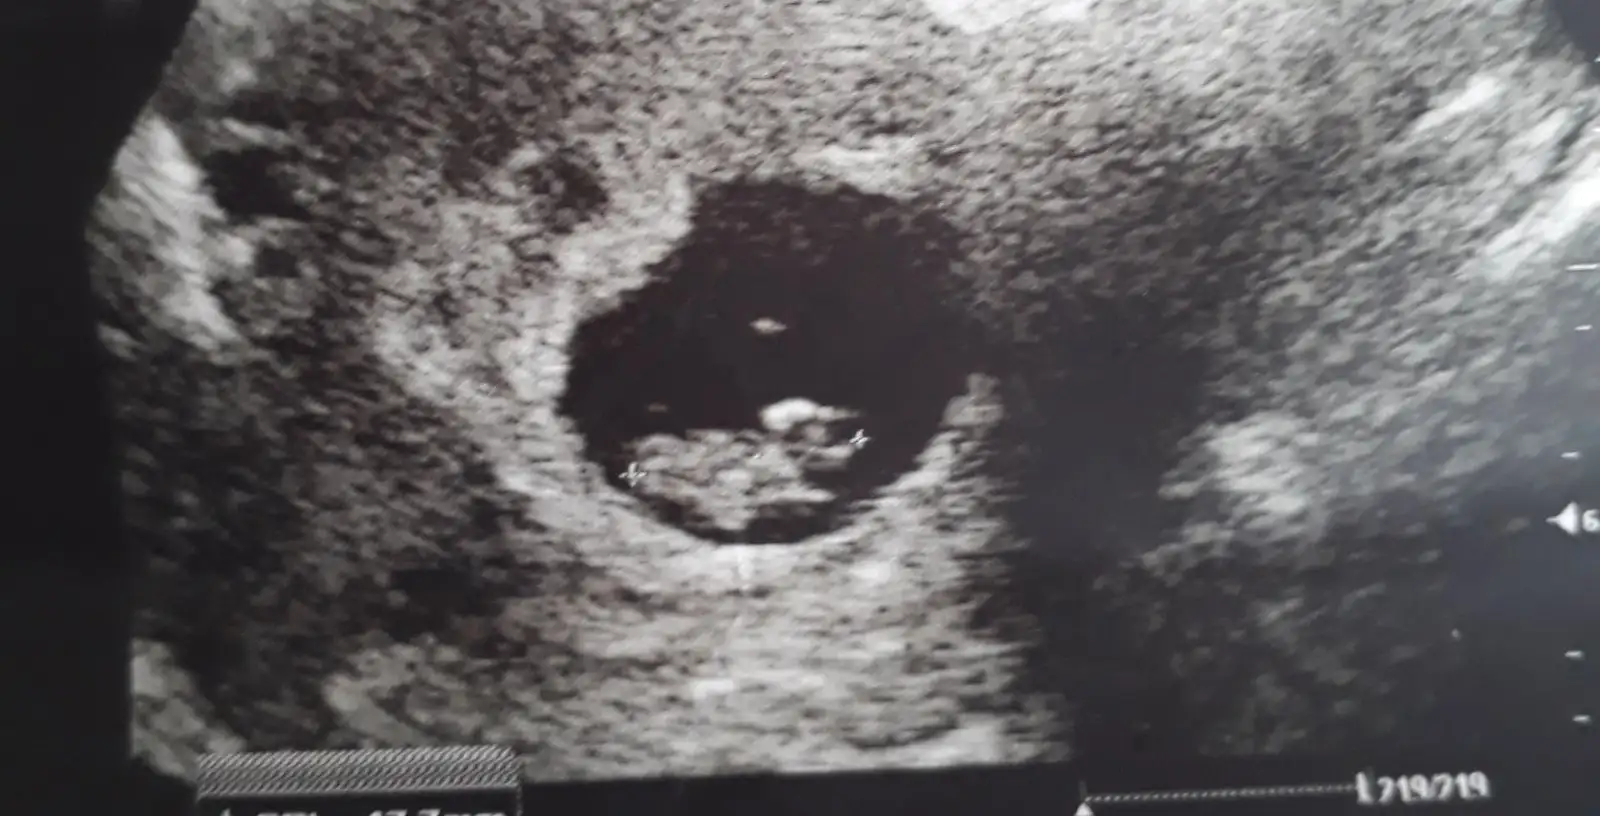

Merhaba arkadaşlar uzun zaman oldu görüşmeyeli nasılsınız biz bugün kalp atımını duyduk şükür darısı bekleyenlerin basina insallahbu da fotoğrafımız 8+0 bugun